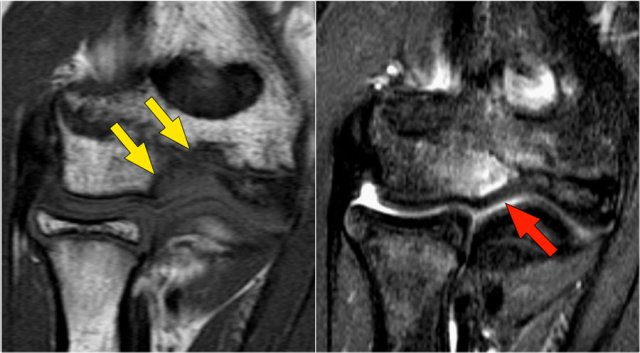

There is a large osteochondral lesion in the lateral trochlea (yellow arrows).

Notice the edema in the subchondral bone (red arrow).

The cartilage is still intact.